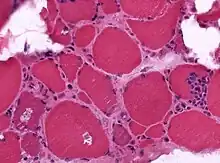

| A muscle biopsy from someone who is diagnosed with myositis. | |

Muscle biopsies, however, are the most reliable tests for diagnosing myositis.[4]